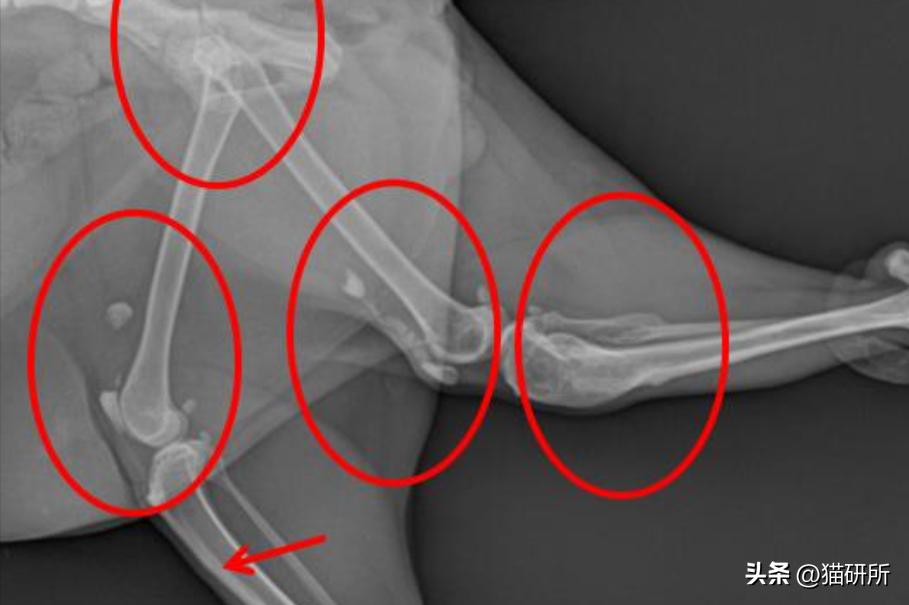

· 出现跛行和髌骨问题的猫咪73%都是双侧髌骨骨折,且40.8%的猫咪除了髌骨骨折,髋臼、胫骨、坐骨、髂骨等地方也出现了1~6次骨折。

红圈为患病猫咪常出现骨折的部位

图自:引文[3]

后续容易发生骨折的部位

a)骨盆;b)胫骨;c)肱骨;d)跟骨